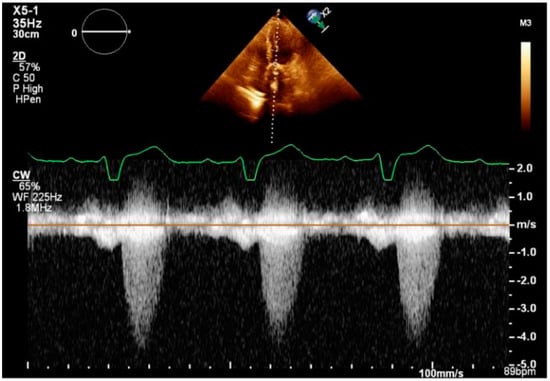

A 68-year-old male with a history of heart failure and reduced ejection fraction (HFrEF), and with a left ventricular ejection fraction (LVEF) of 30%, hypertension, hyperlipidemia, and cirrhosis secondary to nonalcoholic steatotic hepatitis (NASH) was referred for symptomatic severe bioprosthetic aortic valve stenosis. He had a surgical AVR with a 21 mm Carpentier–Edwards PERIMOUNT aortic heart valve 13 years ago, followed by TAVR with a 23 mm Edwards Sapien XT valve three years ago. The bioprosthesis was initially selected because of a concern for the compliance with anticoagulation, and the patient had progressively worsening fatigue and dyspnea on exertion, and the transthoracic echocardiogram (TTE) showed severe aortic stenosis with a peak velocity of 4.1 m/s, mean aortic valve gradient of 40 mmHg and area of 0.78 cm2. The aortic valve velocity is shown in Figure 1. Informed consent was obtained from the patient.

Figure 1.

TTE showing peak aortic valve velocity.